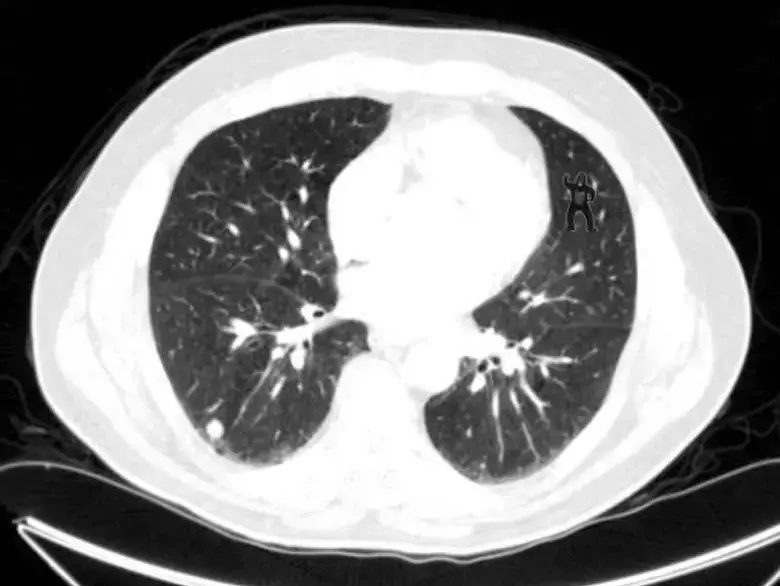

Bunun sonucunda, işleri fark etmek olan profesyonel araştırmacıların bile istem dışı körlük sorunları yaşadıkları anlaşıldı. Yakın tarihli bir çalışmada, araştırmacılar bir grup radyoloğa bir dizi X-ışını taraması verdi. Onlardan akciğer kanseri nodüllerini aramalarını istedi. Bu kişiler için bu görev günlük rutinlerinin bir parçasıydı. Şimdi aşağıdaki görüntüye dikkatle bakın. Garip bir şey fark ettiniz mi?

Ancak radyologların bilmediği bir şey vardı. Aslında araştırmacılar, röntgenlerin içine tipik bir nodülden 48 kat daha büyük bir gorilin görüntüsünü yerleşmişlerdi. Ancak radyologların çoğu bu fark etmedi bile. Simons’un dediği gibi, “Bakmak, görmekle aynı şey değildir. Farkında olmak için dikkatinizi ona odaklamalısınız.”